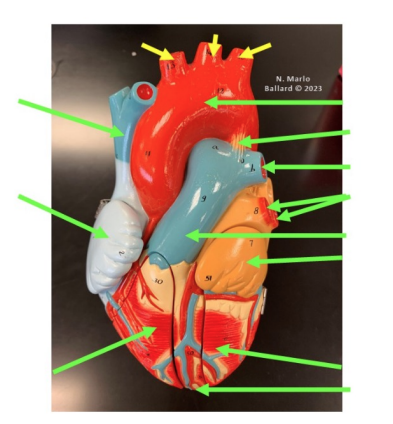

What vessels supply the myocardium?

Coronary arteries

Arise from the Ascending aorta (just above the aortic valve)

Two main arteries:

Right coronary artery

Left coronary artery

Supply oxygenated blood to the myocardium (heart muscle)